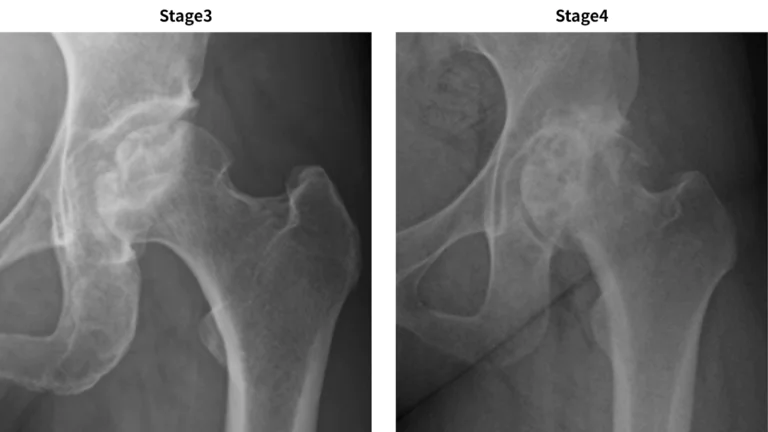

3. Stage 3:骨頭が圧潰。関節裂隙は保たれる。

o 3A:圧潰が3mm未満

o 3B:圧潰が3mm以上

4. Stage 4:関節症性変化が出現。